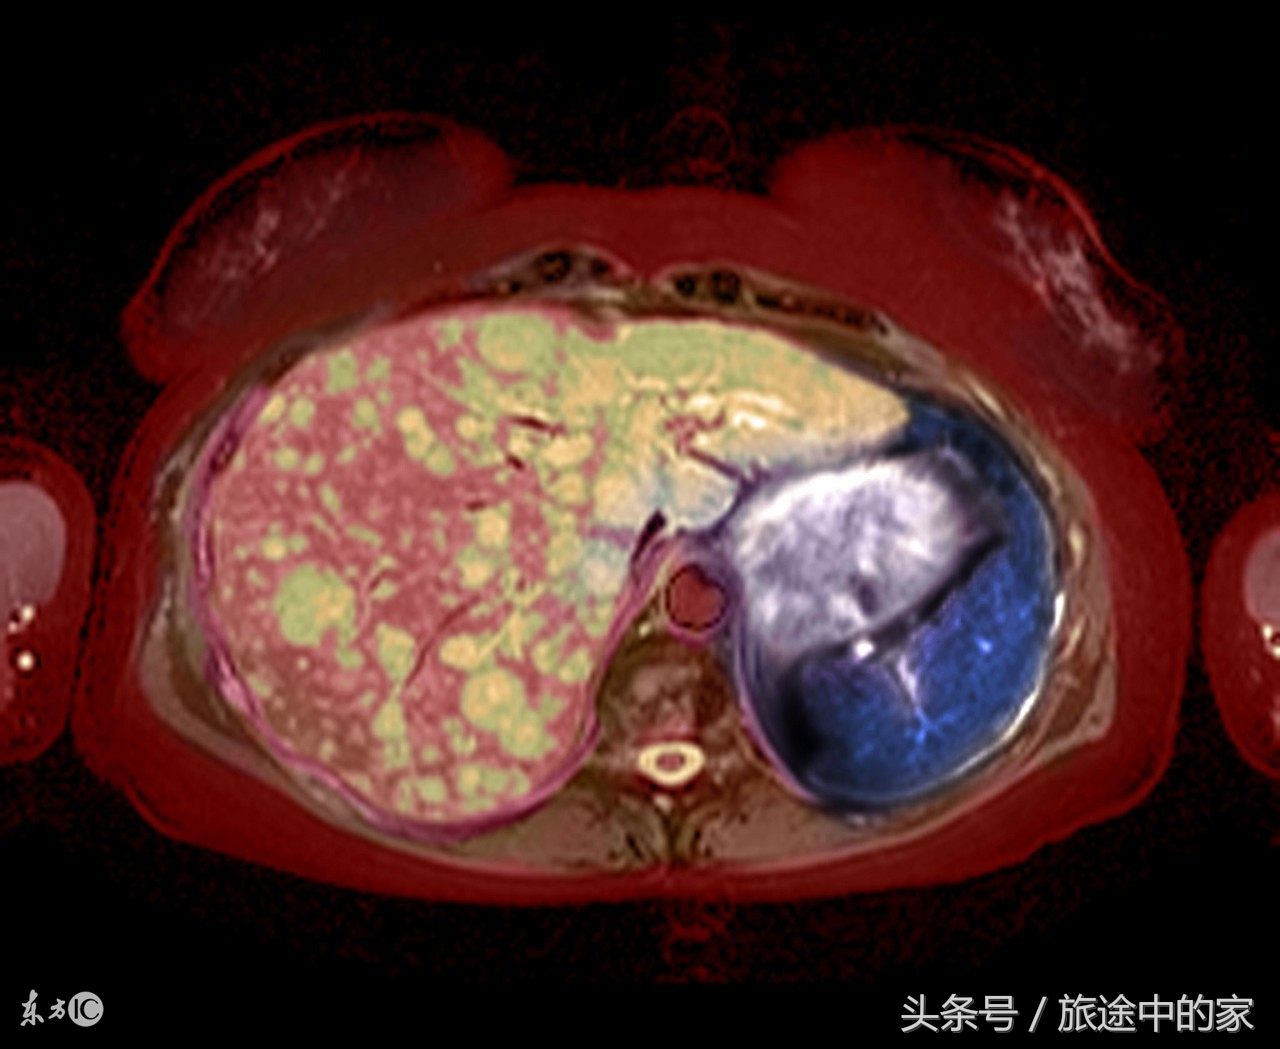

9)肝癌:肝癌对的早期发现很重要,因为肝癌起病隐匿,发展迅速,治疗困难,预后也不好,所以很多肿瘤专家将肝癌称之为“癌中之王”。肝癌早期症状如下:肝区持续性疼痛,痛感为钝痛;食欲降落,容易疲乏,无精打采;腹部闷胀、腹泻、体重降落、越来越消瘦;皮肤和眼球发黄,尿色变黄,且随着时间逐渐加重,这些早期症状与慢性肝炎和肝硬化相似,所以极容易混淆。